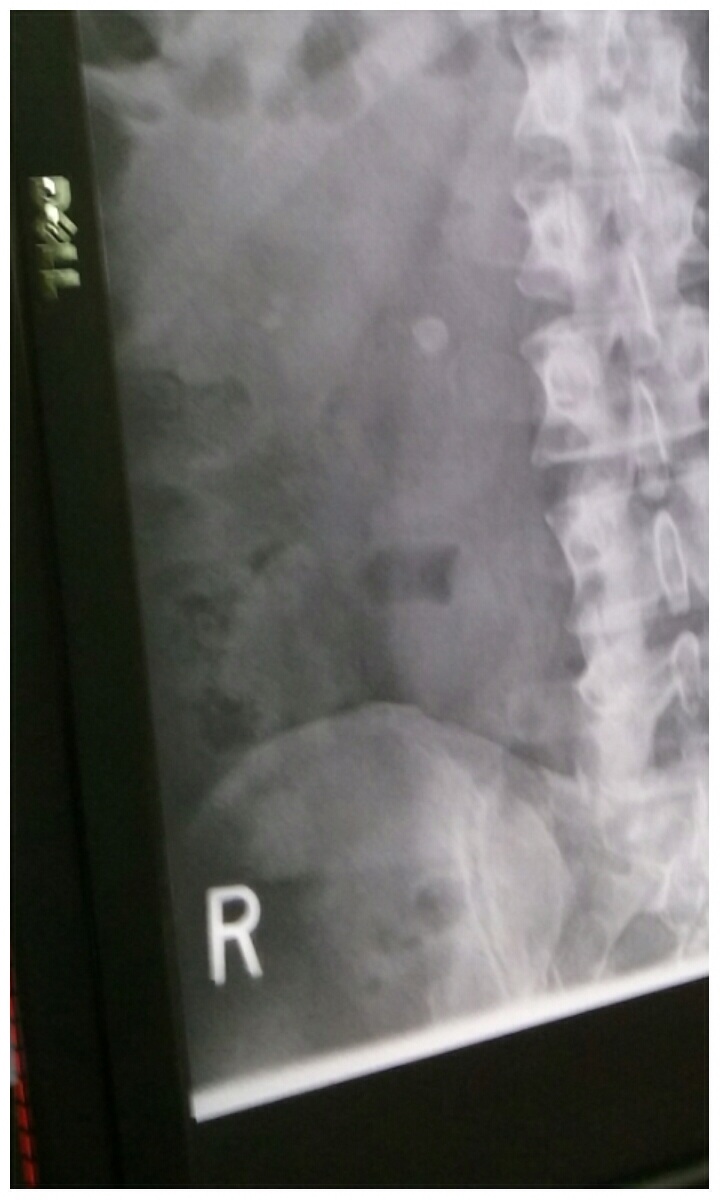

pictured below is the Larger stone on the right and the two smaller stones on the left.